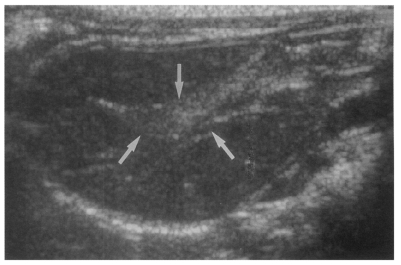

Sonography showed no dilatation of the bile duct confluence in the normal control group (Fig. 3). Sonograms showed moderate or marked dilatation of the bile duct confluence in the primary infection control group, the secondary infection control group, and the reinfection II group (Fig. 4, Table 2). A small number (1 of 7 in all groups) of animals showed mild dilatation of bile duct confluence in these groups (Fig. 5, Table 2). Dilated extrahepatic bile ducts were also observed. In the reinfection I group and the infection following immunization group, the degree of dilatation of the bile duct confluence was usually moderate (in n = 4 and n = 5, respectively). Marked dilatation was less frequent in these groups (n = 2 in each group).

High echogenicity closely packed at the dilated bile duct confluence was seen in all rats in the primary or secondary infection control groups; however, this was seldom noted in the reinfection I (n = 1) and reinfection II groups (n = 0) (p = 0.005 and p = 0.001, respectively) (Fig. 6). The echogenic mass was found to be composed of clusters of worms and desquamated materials by pathological examination. Small echogenic foci were noted in the dilated bile duct confluence in the infection following immunization group. These also represented worms and desquamated materials (Fig. 7). In the reinfection I and II groups, the degree of dilatation of the bile duct confluence on the last follow-up sonograms at 26 weeks after reinfection were noted to be slightly milder than those at 6 weeks after reinfection, but this was not significant (p = 0.266 and p = 0.431, respectively) (Table 2).

Fig. 6

Sonogram of a rat in the reinfection I group 6 weeks after reinfection (13 weeks after treatment), showing an empty dilated bile duct confluence (arrows). Neither worms nor desquamated materials were found.

Fig. 7

Sonogram of a rat in the infection following immunization group 6 weeks after C. sinensis challenge, showing a few small echogenic foci (arrows), indicating worms or desquamated materials in the dilated bile duct.